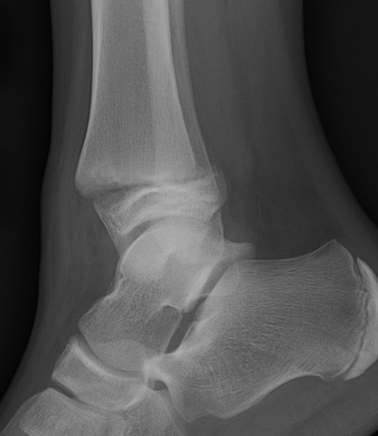

Salter Harris III / Tillaux

Definition

- SHIII of anterolateral distal tibia

- epiphyseal avulsion of AITFL

- supination / ER injury

Incidence

- usually near skeletal maturity

- transitional fracture

- as distal tibial physis is closing

- anterolateral fragment is last to close

Management

ORIF

- reduce articular step / prevent physeal bar

- anterolateral incision to reduce

- either anterolateral 4 mm cannulated screw or

- place screw percutaneously from medial side